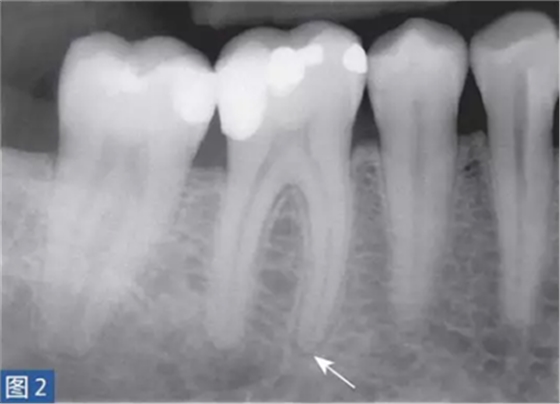

從牙髓炎過(guò)渡到根尖周炎(圖2 和3)的發(fā)生速度非???,牙齒表現(xiàn)可能從正常到對(duì)冷、熱和電刺激的反應(yīng)越來(lái)越強(qiáng)。當(dāng)牙髓已經(jīng)完全壞死時(shí),通常會(huì)顯示對(duì)牙髓電活力測(cè)試無(wú)反應(yīng)。牙齒可能會(huì)有伸長(zhǎng)感,用手指或口鏡柄施加壓力或者振動(dòng)牙齒會(huì)觸發(fā)非常嚴(yán)重的疼痛。放射學(xué)檢查可能存在透射區(qū)及根周膜間隙增寬,通常硬骨板和牙周韌帶沒(méi)有病理學(xué)特征。

圖2: 46 牙齒SAP。術(shù)前X 線片,該牙齒在其他醫(yī)生處已行齲齒治療。患者訴牙齒有明顯的咬合痛以及強(qiáng)烈的冷熱刺激敏感癥狀。放射學(xué)檢查,近中根根周膜間隙略增寬。

圖3: 46 牙齒SAP。根管治療6個(gè)月后。